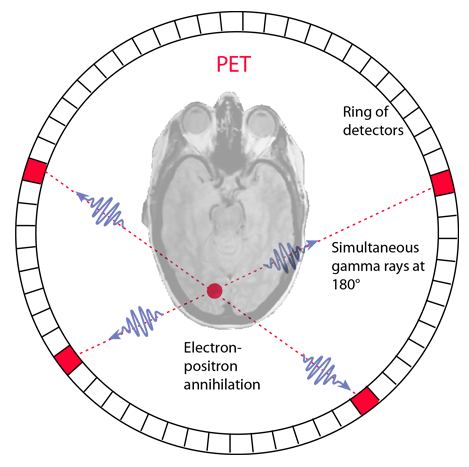

An interesting application in nuclear medicine is the use of positron annihilation in positron emission tomography or PET. Certain radioisotopes decay by positron emission, and such radioisotopes can be used as tracers. If injected into the body, they can be readily followed because the emission of the annihilation pairs of coincident gamma rays at 180° allows their source to be located along a line. Data collection for emissions at several angles permits precise location of any concentration of the radioisotope. An image of a slice of the body (called a tomograph) can be constructed by using a ring of detectors.

When a positron is emitted by a nucleus, it almost instantly finds an electron and the pair annihilates, converting all the mass energy of the two particles into two gamma rays. The two gamma ray photons possess momentum, and the conservation of momentum requires that they travel in opposite directions. A simultaneous detection of gamma ray photons in two detectors places the source on a line between those detectors.

| For a given location, you can sum the signal from all detector pairs that correspond to a line going through that location. All directions are equally probable for a given location, so you can normalize the signal as a measure of the concentration of the radioisotope at that location. |